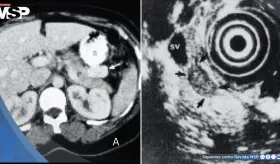

Paciente presenta ruptura intraperitoneal de quiste parasitario después de presión abdominal súbita, manifestando dolor intenso en hipocondrio derecho con irradiación al hombro.